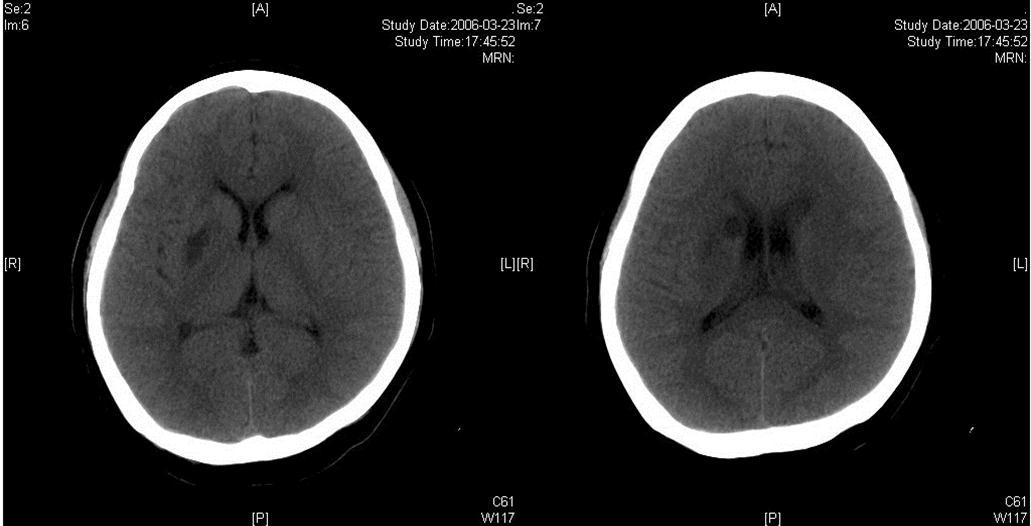

The same dose of aspirin, clopidogrel and subcutaneous LMWH was used after the operation. Two days after the stenting (Mar 23), three successive bouts of left limb weakness along with slight dizziness occurred, lasting about 10 minutes with intervals of 30 minutes. There were no abnormal signs between the first and second attacks. Babinski sign was noted during the second attack and persisted in the left between the second and third attacks with normal muscle strength, but she felt weakness. Blood pressure was 140/70 mmHg. After the third attack, her tongue deviated slightly to the left side. There was slight decrease in muscle strength and Babinski sign was positive in the left. Emergent CT displayed two low density lesions with clear edge and homogeneous density in the right basal ganglia (Figure 3). Aspirin 300mg was given emergently. Compared with the Transcranial Doppler (TCD) test before the operation (March 3), emergent TCD showed the blood flow velocity increased significantly in both anterior cerebral artery (ACA), especially in right ACA (Table 1). She got partial recovery after being given volume expansion treatment with low molecular dextran. Then she was given anticoagulant treatment with intravenous unfractionated heparin (UFH) (500 U/h). LMWH was stopped. On the next day, her muscle strength recovered to normal, but pathological sign persisted. Anticoagulation therapy was continued along with dual antiplatelet therapy. On Mar 25, limb weakness appeared again, muscle strength was Ⅳ grade in the left, both Babinski sign and Chaddock sign were positive. Volume expansion with low molecular dextran was ineffective, and the dose of UFH was increased to750 U/h. Two days later, muscle strength and plantar reflex recovered to normal. On Mar 27, CT scan revealed that the lesion did not change compared with the previous scan, and there was no new lesion. Dose of UFH was reduced to 500H/h. During treatment, blood coagulation test was performed for several times, PT was stabled at 14.1~15.5 sec, APTT at 32.7~43.1 sec, INR at 66.6%~78.8%, activity of antithrombin Ⅲ (AT Ⅲ) at 70.4%~97.2%, and fibrinogen at 3.93~4.68 g/L. UFH was replaced by LMWH on Mar 31. CTA (Apr 3) displayed the stent was in M1 segment of right MCA, its proximal lumen was attenuated compared with the left MCA, with slightly compromised distal blood flow (Figure 4).

Figure 3.Two infarcts displayed in CT images

The right MCA stenosis, which led to the transient ischemic attack (TIA) symptoms, was definitely diagnosed. Angioplasty and stenting was conducted after full preparation of dual anti-platelet therapy. Immediately before the operation, LMWH was used in combination and was continued after operation. Her condition was stable in the first two days after operation. Then crescendo TIA recurred and led to motor impairment. Two lesions were shown in the emergent CT images. One was near the anterior horn of the right lateral ventricle, by which it was difficult to explain the symptoms and physical signs. The other was in basal ganglia, and was related to the symptoms and signs. The signal in this region had been slightly higher than the counterpart in the left in the source image of MRA before operation. Hence the lesion in basal ganglia was thought to result from hemodynamic impairment in distal parts of stenotic MCA. Both lesions had clear boundaries, which indicated that the infarction in the area supplied by deep branch of MCA occurred before the TIA attacks. The crescendo TIA worsened gradually, but got partial recovery after volume expansion treatment initially. TCD test showed the blood flow velocity increased in both ACA, especially in the right, while that in the right MCA did not significantly increase. This indicated that some collateral circulation had formed, to counteract hypoperfusion caused by progressive stenosis in the right MCA. Based on these, we deduced that there was IST which did not completely block the right MCA. The symptoms and physical signs appeared again when there was failure of collateral compensation. Because there were new lesions on CT scan and the patient had been treated with dual anti-platelet treatment and anticoagulation, thrombolytic therapy could not be given. So we gave unfractionated heparin (UFH). The symptoms and physical signs disappeared on the next day. But two days later during the same treatment, the symptoms and signs recurred, volume expansion was ineffective, this indicated that initial recovery of symptoms was due to compensatory collateral circulation, and anticoagulation therapy with UFH may also play a role. But this could not prevent thrombosis from progressing, so we increased the dose of anticoagulation drugs, the symptoms and signs disappeared eventually. CTA (Apr 3) and repeated TCD (Apr 17) confirmed our reasoning with attenuated proximal lumen of right MCA and increased blood flow velocities of the right MCA and ICA.